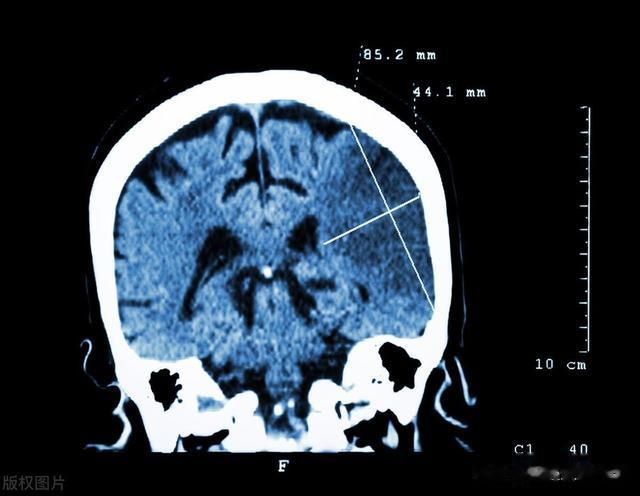

脑梗的发生是因为血液中的血栓阻塞了脑部的血管,导致大脑某些区域缺血缺氧。负责手部运动的神经如果受到影响,患者就会出现手部动作失调、无力的现象。